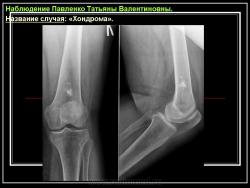

Энхондрома (син.: хондрома, центральная хондрома) — доброкачественная хрящевая опухоль, расположенная в костномозговом канале (интрамедуллярно). Встречается в 10 % случаев от общего числа доброкачественных опухолей костей. Считается, что она возникает из эктопически расположенных островков хряща, отщепившегося от пластинки роста на ранних этапах онтогенеза. В ряде случаев опухоль остается бессимптомной и обнаруживается случайно при рентгенологическом исследовании. В других случаях возникают боль и припухлость. Обычно болезненными становятся все энхондромы фаланг. Наиболее частая локализация: фаланги, главным образом, пальцев кистей, проксимальный конец плечевой кости, проксимальный или дистальный концы бедренной кости. При рентгенологическом исследовании в энхондроме определяются просветления с участками минерализации. Тень кости становится более широкой, кортикальный слой сохраняет целостность, но истончается. В редких случаях энхондрома имеет вид эксцентрически растущего экзофитного новообразования. Макроскопически опухоль представляет собой голубовато-белую полупрозрачную хрящевую ткань, в которую вкраплены желтоватые участки обызвествления. Опухоль состоит из отдельных хрящевых узелков, диаметр которых варьирует в пределах 1 см.

Рентгенологическая картина хондромы представляет четко очерченный опухолевый узел. Очаги минерализации в хондромах выглядят достаточно характерно и представлены очаговыми, глыбчатыми или кольцевидными , арочными отложениями извести. Полного разрушения кортикального слоя трубчатой кости с выходом опухолевых масс в мягкие ткани не наблюдается.